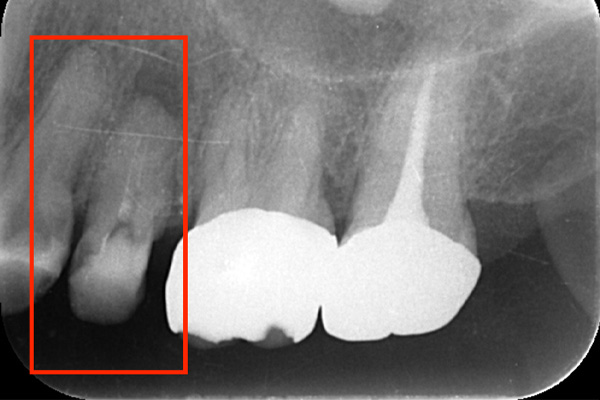

こちらは、歯の根の治療を行い、根の先端までキレイにし、防腐剤をしっかり詰めなおしましたが、膿が溜まったまま治癒しませんでした。破折に気づけなかったのです。

破折に気づいてからは、抜歯を行い、インプラントを入れてまた噛める様にしていきました。レントゲンでも破折がわからない時があります。そんな時はCTやマイクロスコープを使うとわかることが多いのです。